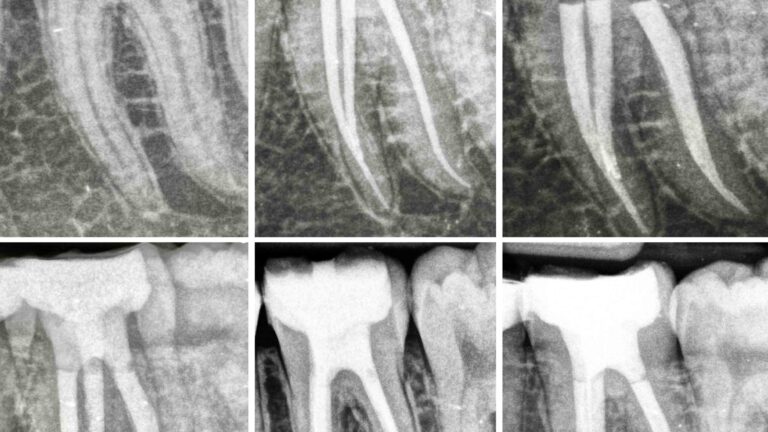

Retratamiento de un primer molar superior con 5 conductos con RetreatAll Conocer fielmente la anatomía interna de los…